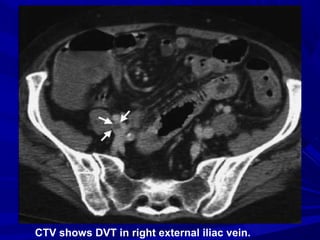

 Contrast-enhanced CT of LL veins

can be performed using the same

contrast bolus used for CTPA.

 Images of the iliac, femoral, and

popliteal veins are obtained 4

minutes after the onset of contrast

injection.

CTV shows DVT in right external iliac vein.

CTV shows DVTin right external iliac vein.